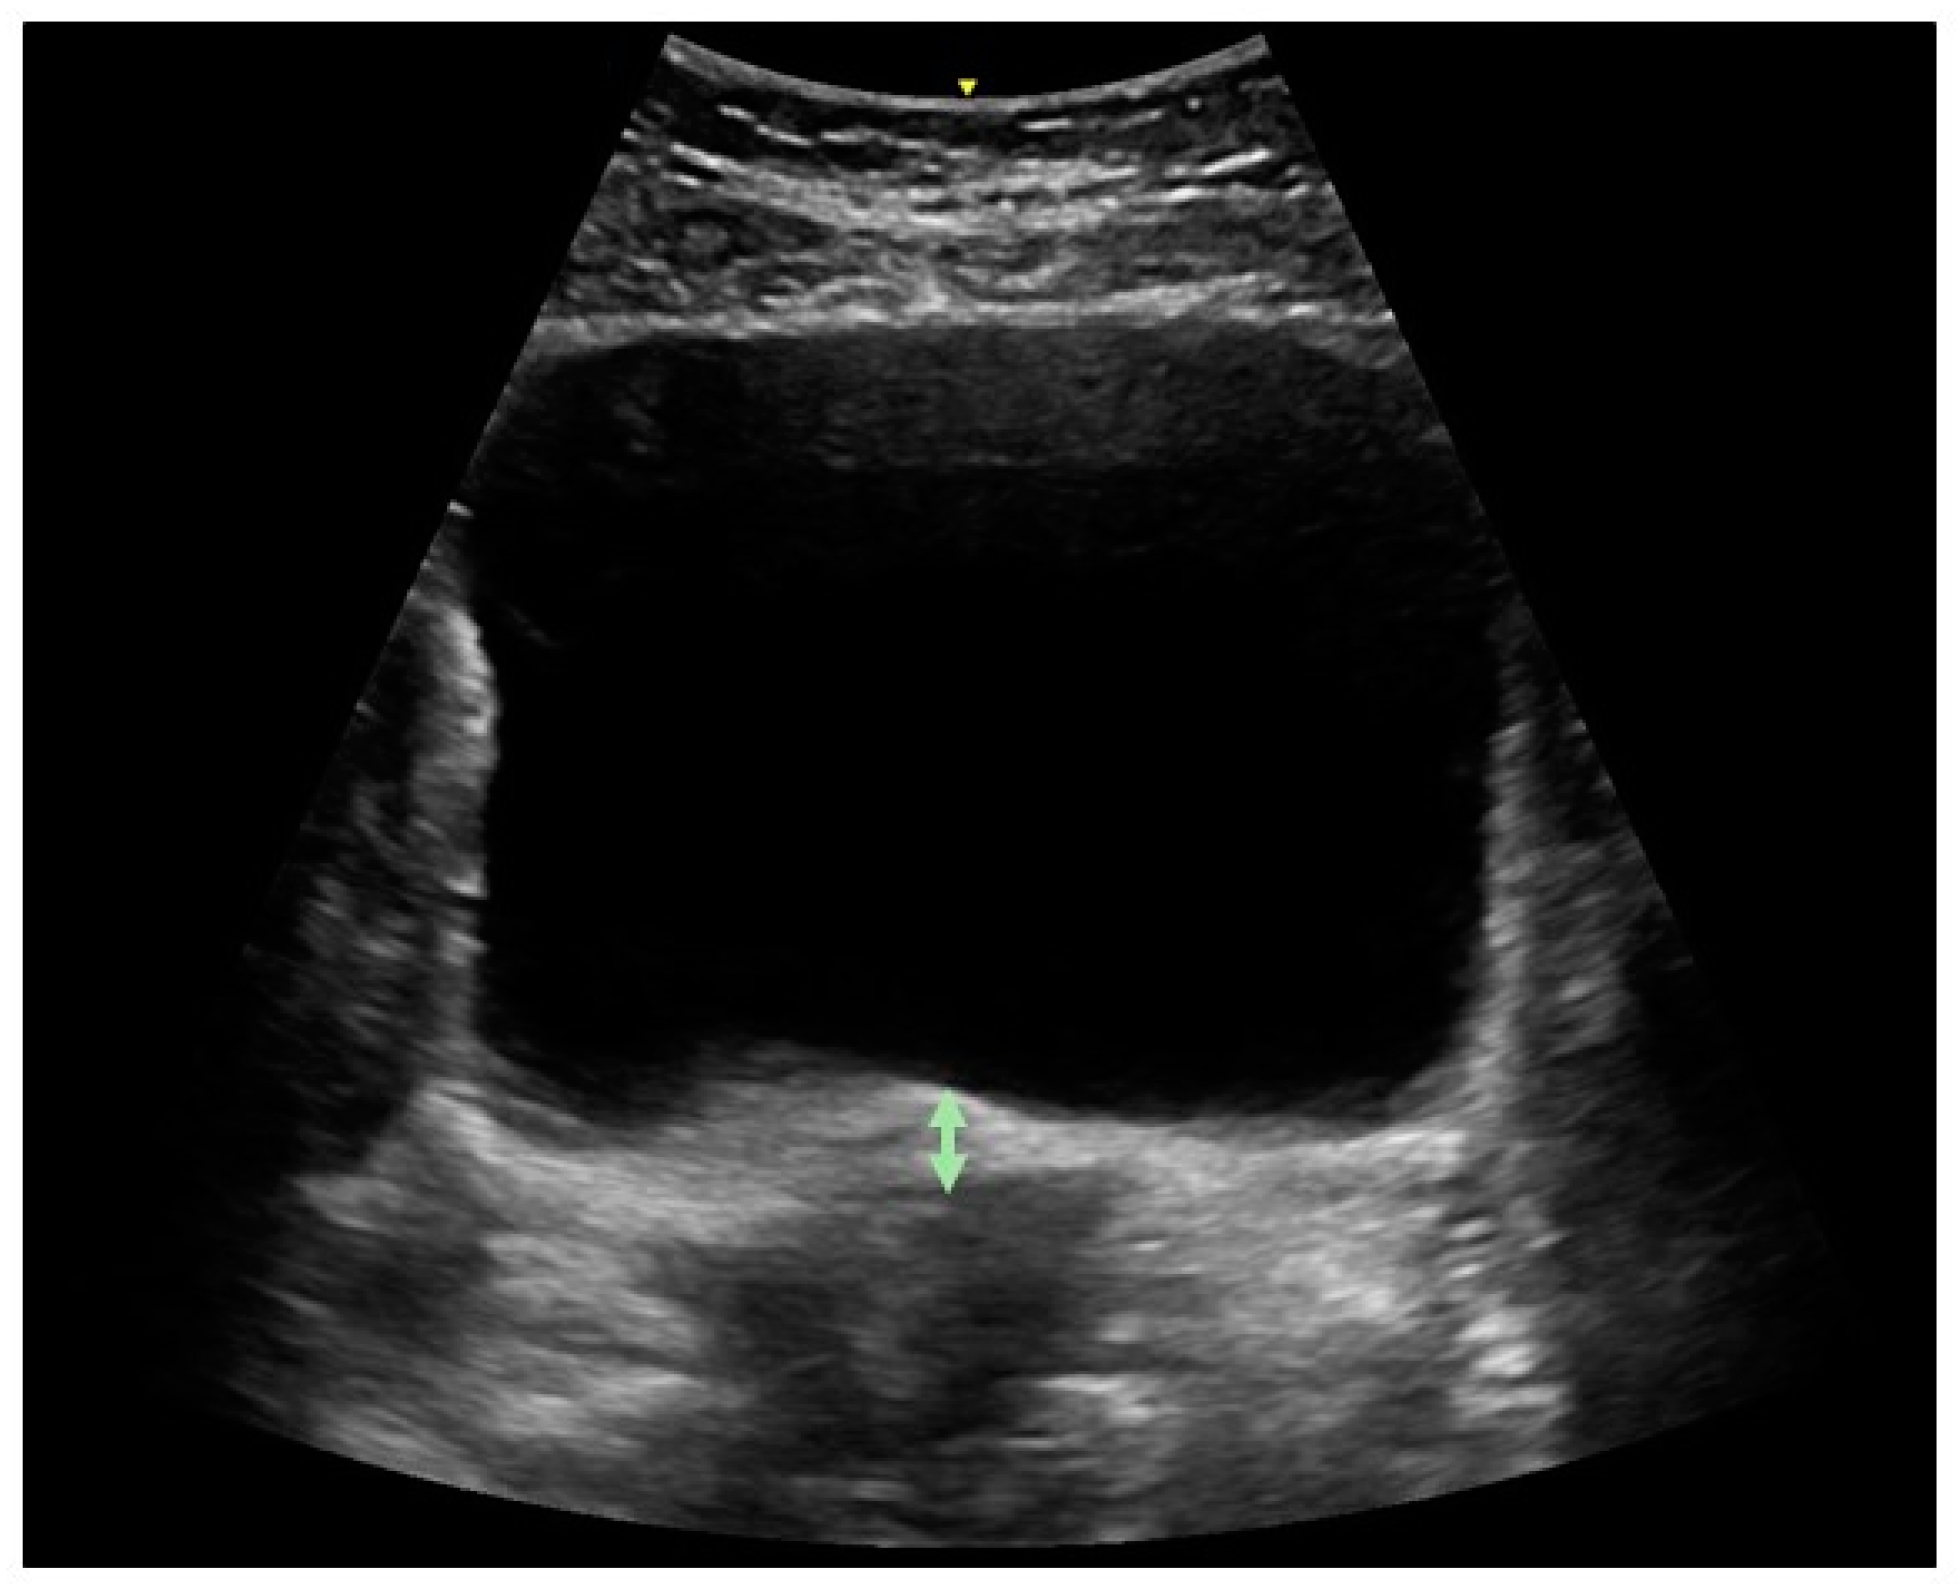

In all positions, the ultrasound transducer was placed in the transverse plane immediately supra-pubically over the lower abdomen at a 15–30° angle from the horizontal plane. The bladder base was marked with the online caliper tool of the device [23,24]. Participants were directed to perform a pelvic floor muscle contraction and the examiner assessed if a correct contraction (upward displacement of the bladder base) was performed, and then measured bladder base displacement (in mm) (Figure 1). In each position, two contractions were maximum voluntary contractions, and the third contraction examined endurance. The participant was instructed to hold the contraction as long as she could (measured in sec). If the contraction exceeded 30 s, she was instructed to stop.

Figure 1. Ultrasound examination of pelvic floor muscle function as assessed by displacement of bladder base from rest to contraction. Upward movement occurs during correct contraction.